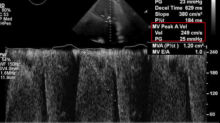

The patient was a 76-year-old woman with a known history of mitral stenosis. Her symptoms included worsening fatigue, malaise, and dyspnea with exertion. Echocardiography demonstrated a mitral valve area of 0.7 cm2 with a mean mitral valve gradient of 25 mm Hg, classifying this as severe mitral stenosis. The heavily calcified leaflets precluded a mitral valve repair and it was felt that the annular calcifications prohibited traditional mitral valve replacement. Thus, the authors proceeded with surgical mitral valve replacement with a transcatheter bioprosthetic valve.

The left atriotomy was closed and ventricular and atrial pacing wires were placed. The patient was weaned from bypass without concern and immediate on table TEE demonstrated low mitral valve gradients. The post placement 3D echocardiogram demonstrated a much-improved mitral valve orifice with clearance of the calcifications. There were no downstream effects on the aortic valve. The patient required pacemaker placement on postoperative day two for persistent bradycardia, however the remainder of her hospital stay was uneventful. They obtained a TTE prior to discharge, demonstrating appropriate valve placement with a mean gradient of 6 mm of Hg and an EF of 55-60%.